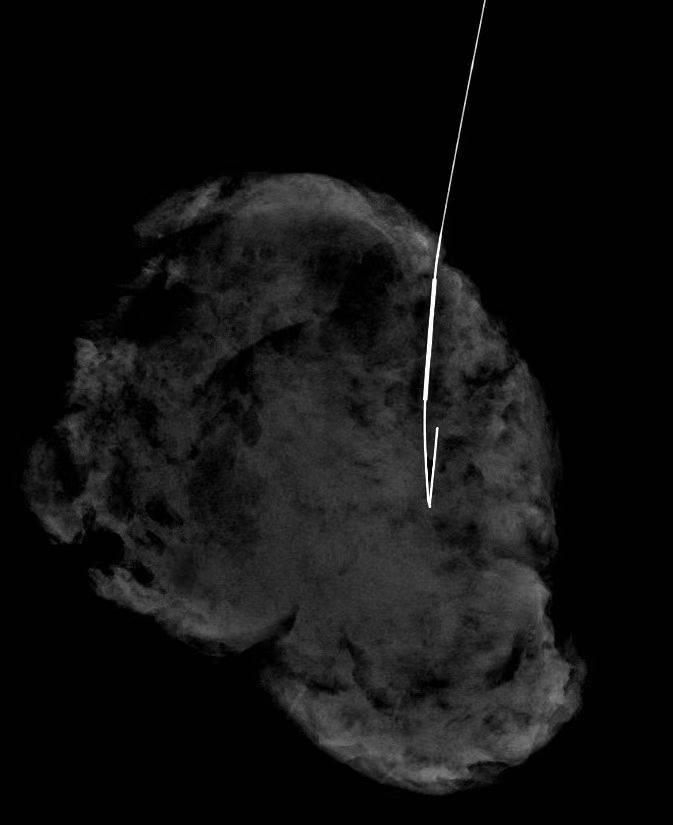

在技术员张云及黄纯莉等医师的通力配合下,定位针准确穿入病灶内,并调整好位置,为手术的顺利进行做好前期保障工作。

对于临床不可触及、超声阴性仅钼靶X线显示结构扭曲及钙化的病变,在乳腺X线引导下术前定位,可使病变部位得以准确标记,有助于评估病灶范围,指导外科精准切除病灶,最大限度的保留正常腺体,避免良性病变过度手术或恶性病变漏切给患者带来的身体损伤和心理负担。提高了乳癌早期诊治疗效,减低乳腺癌死亡率,更提高了乳腺手术的安全性及保乳手术的开展率。